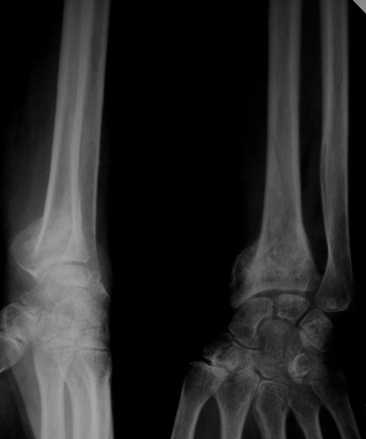

Уважаемые коллеги! Обратилась женщина, 55 лет. Травма 3 месяца назад, лечилась по месту жительства (Рис.1). Косорукость, боли, ограничение движений.

Досняли - рис.2-6. Хотелось-бы услышать мнения об объеме операции. С уважением, Юрий Алексеевич Булахтинглавный травматолог Камчатского Военно-морского госпиталя

u pazientki po nauchnomu ulna abutment/impingment syndrome posle posttraumaticheskogo ukorochenia radiusa

na rengene znachitelnoe ukorochenie radiusa, sustavnaia poverchnost naklonena dorsalno chresmerno , chetko vidno nekongruentnost DRUJ - distalnogo radioulnarnogo sustava ,ulna prosto vtikaetsia v triquetrum .